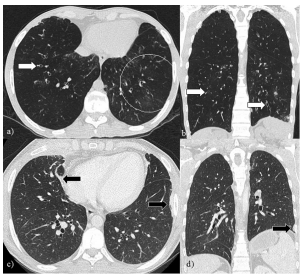

Existen reportes de pacientes que iniciaron su clínica con signos y síntomas de BOS que subsecuentemente, en su evolución, desarrollaron cambios fibróticos en la TCMD compatibles con SER, lo que los clasifica dentro de este fenotipo2. El re-trasplante pulmonar es la única alternativa terapéutica para pacientes en estadío final de estos fenotipos de DPCI3. Figura 3